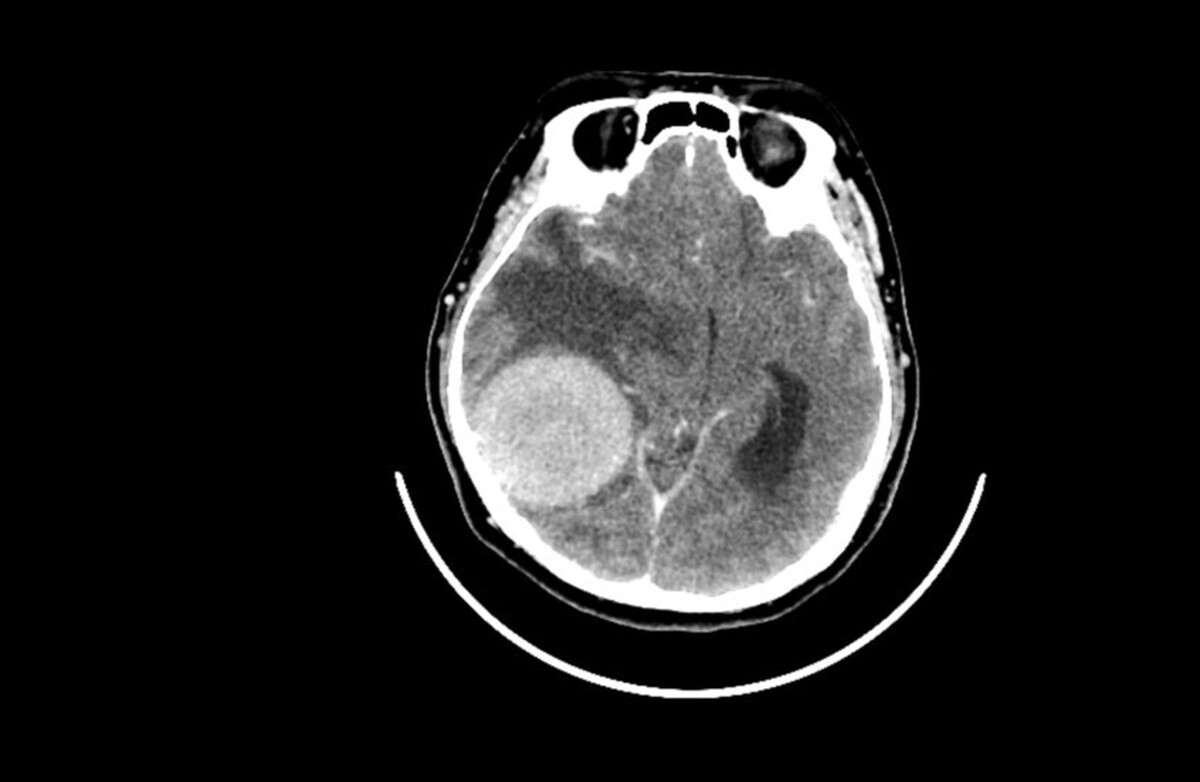

مطالعه تکان دهنده: اضطراب و سرگیجه با تومور‌های مغزی مرتبط هستند!

یک مطالعه اخیر ارتباطی بین اضطراب و سرگیجه از یک سو و تومور‌های خوش‌خیم مغزی از سوی دیگر پیدا کرده است.

شوانوم دهلیزی، که با نام نوروم آکوستیک (تومور خوش‌خیم و با رشد آهسته عصب مسئول شنوایی و تعادل) نیز شناخته می‌شود، معمولاً با علائمی مانند کاهش شنوایی، وزوز گوش و سرگیجه همراه است. با این حال، مطالعه جدید نشان می‌دهد که عوامل روانشناختی نقش محوری در شدت این علائم دارند.